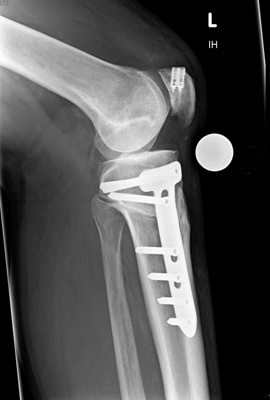

Dr. med. Alexander Strehl: Bei der häufigsten Umstellungsosteotomie am Unterschenkelkopf macht man einen Sägeschnitt am Knochen, klappt diesen gezielt auf und fixiert ihn mit einer winkelstabilen Platte; dies auf Basis dessen, was man vor der Operation bei der Planung gemessen und errechnet hat. Es entsteht ein winkelförmiger Spalt im Knochen, der von selber wieder zuwächst. Je nach Ort und Art der Deformität findet auch der Eingriff statt. Bei einem O-Bein ist dies meistens am Unterschenkelkopf. Es können aber auch Eingriffe am Oberschenkel nötig sein, vor allem beim X-Bein. Bei extremen Deformitäten kann auch eine Doppelosteotomie erforderlich sein, also dass man am Ober- und Unterschenkel korrigieren muss, um wieder eine gerade Achse zu erhalten. Dies muss man im Vorfeld genau analysieren und planen. Während der Operation wird die Beinachse mehrfach mit dem Ausrichtestab überprüft.

Bei Patienten ohne Voroperationen dauert der Eingriff unter zwei Stunden. Bei Voroperationen und vorhandenen Vernarbungen dauert es eventuell länger, da es schwieriger ist, alles zu lösen, um den Knochen aufzuklappen. Eine Doppelosteotomie dauert drei bis vier Stunden.

Dr. med. Alexander Strehl: Der Patient bleibt vier bis fünf Tage in der Klinik. Danach sind sechs Wochen Gehstöcke mit Teilbelastung angesagt. Wie stark der Patient mit den Stöcken belasten darf, hängt davon ab, wie stabil sich der Knochen während der Operation gezeigt hat und wie stark seine Beschwerden sind. Es folgt Physiotherapie, da es wichtig ist, dass das Gelenk gut beweglich bleibt. Nach sechs Wochen wird ohne Gehstöcke aufbelastet.